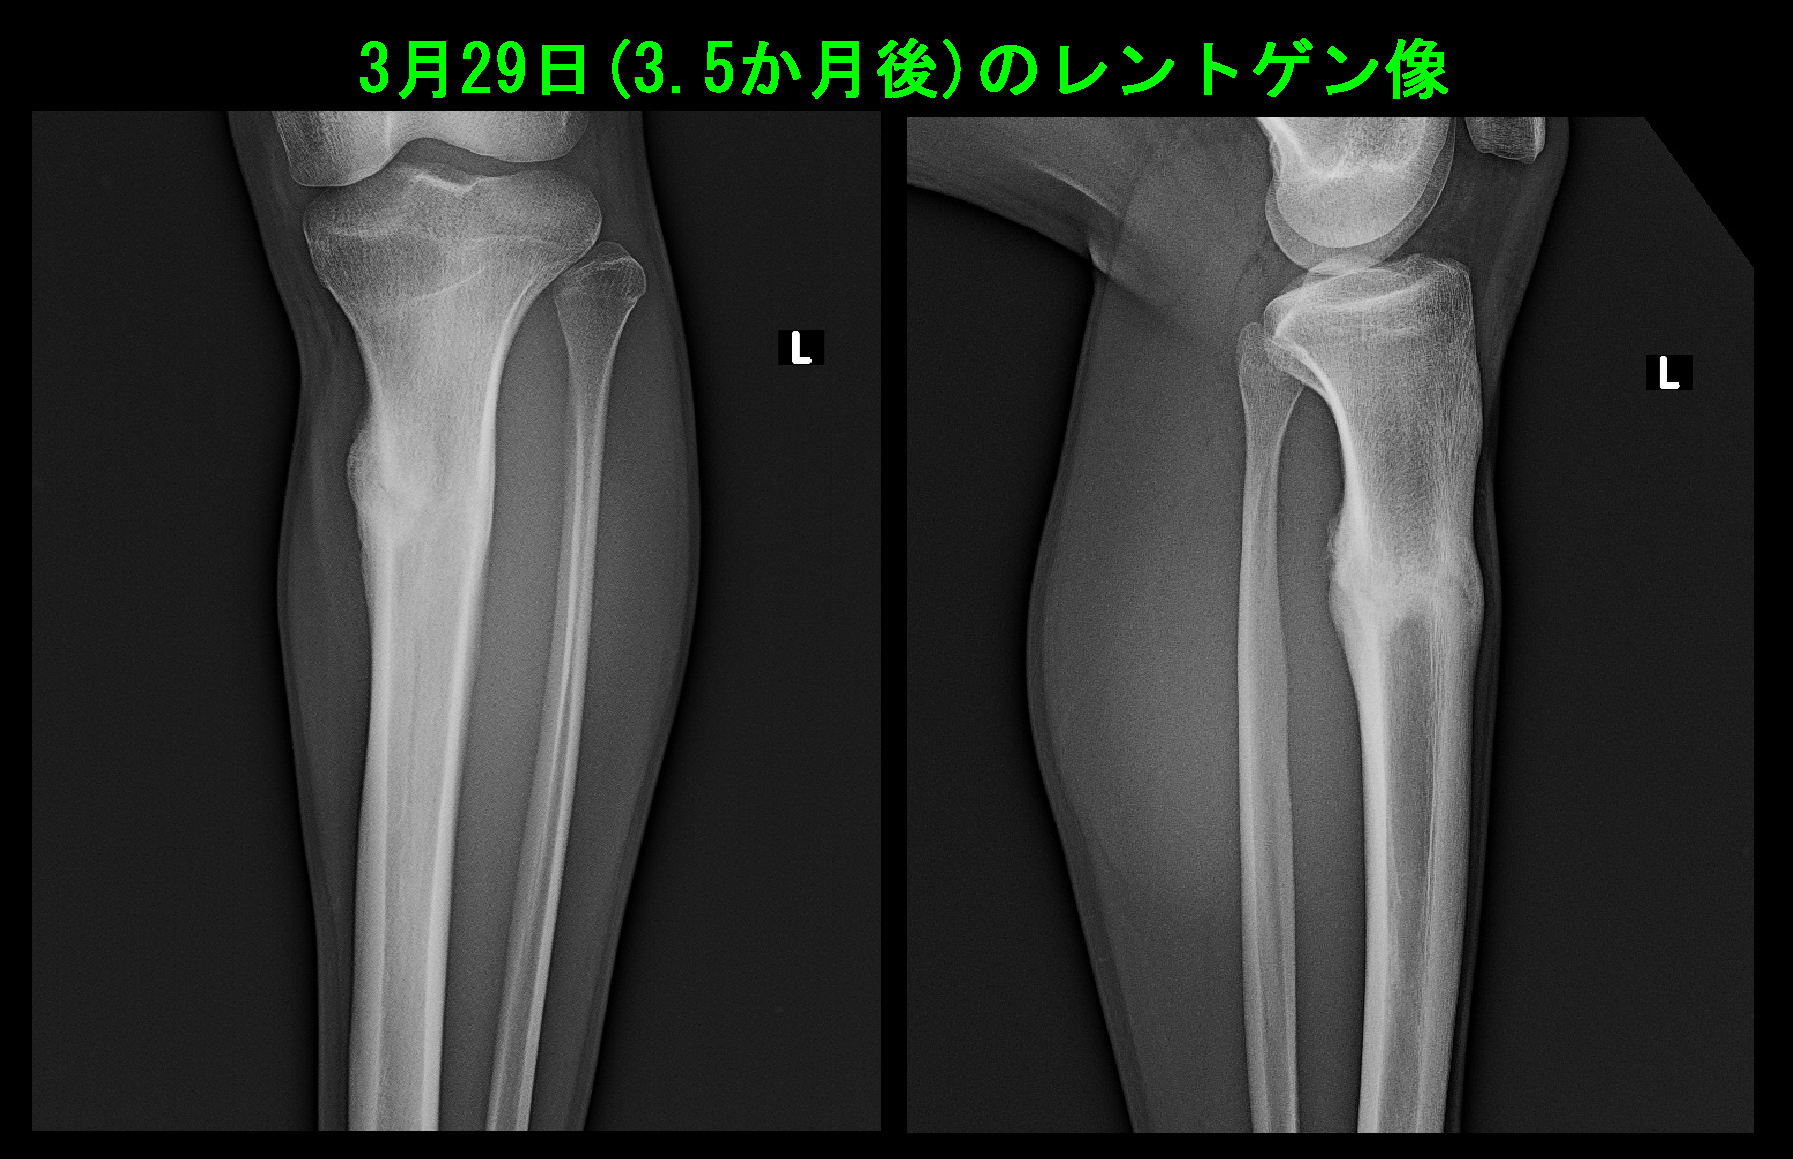

初診時MRI検査.jpg

MRI検査ではSTIRという骨が黒く見える条件で、脛骨の同部は白く損傷を起こし、出血している所見でした。

骨の周囲が白いのも骨を覆っている骨膜が炎症を起こしている所見です。

脛骨の疲労骨折と診断し、最低6週間の練習休止を指示しました。